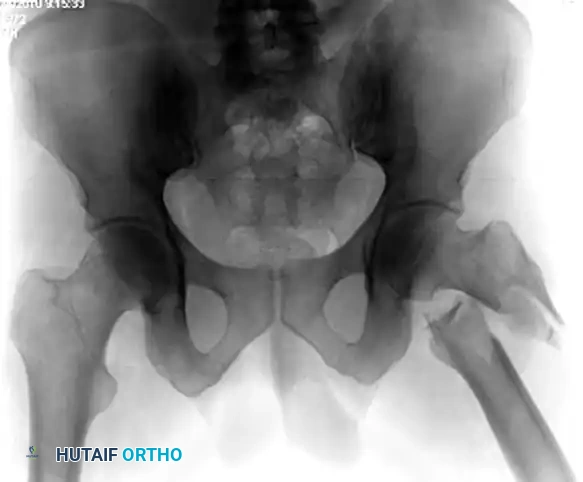

Figure A: Preoperative radiograph demonstrating the classic flexion, abduction, and external rotation deformity of the proximal subtrochanteric fragment.